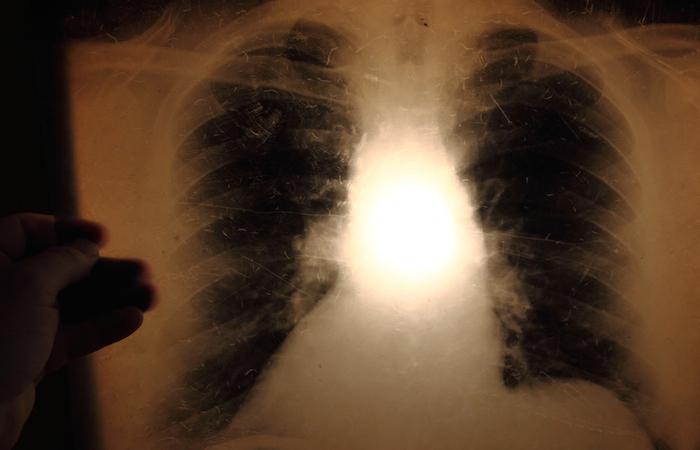

Le vaccin antituberculeux actuel, dérivé d’une souche bovine, protège mal les adultes de la forme la plus contagieuse de la maladie, la tuberculose pulmonaire. Or, plus de 10 millions de personnes l'ont contractée en 2015. Après examen attentif du du mode d'action de la maladie avec ou sans vaccin, les chercheurs ont mis en évidence un mécanisme naturel que ne reproduit pas le BCG.